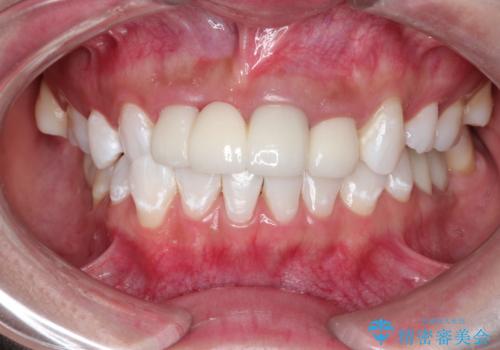

- 特に症状など気になるところはないが、メンテナンスして欲しいとのことでした。染め出しをしてのブラッシング指導とPMTC30分コースを行いました。

磨き残しが多くなると、お口の健康を維持していくのが難しくなってしまいます。お口の健康を守っていくためには、毎日のハミガキを行っていくのが基本です。そのため、なにか症状がなくても定期的に歯科医院で口の健康状態のチェックをすることが大切です。